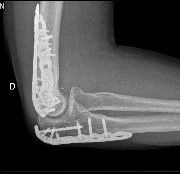

Post-opératoire (6 mois)

Fracture complexe du coude